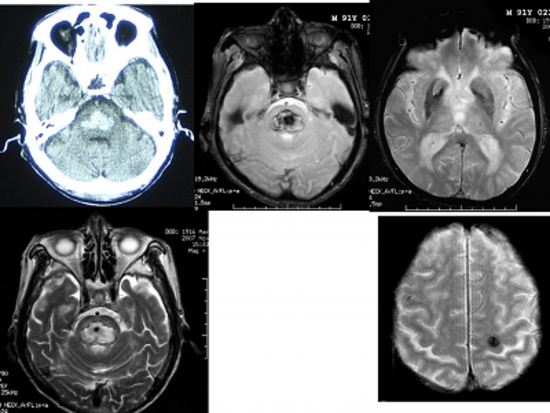

Figure 1

Head CT, MRI T2*-weighted image, T2-weighted image of acute pontine hemorrhage.

In the T2*-weighted images (three images on the right), the acute hemorrhage appears black around and white inside, while the hidden cerebral hemorrhage looks like a ball of black thread.